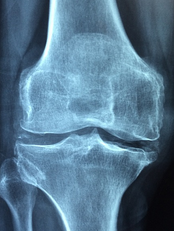

msm 하루 권장량 및 효능에 대해 알아보도록 하겠습니다. MSM은 메틸설포닐메테인의 약자로, 식이유황이라고도 불립니다. MSM은 식물성 유지나 생선 등에 함유되어 있는 천연 유기 유황 화합물로, 인체 내에서도 자연적으로 생성되는 물질입니다. MSM은 관절과 연골 건강에 도움을 주는 성분으로 알려져 있습니다.